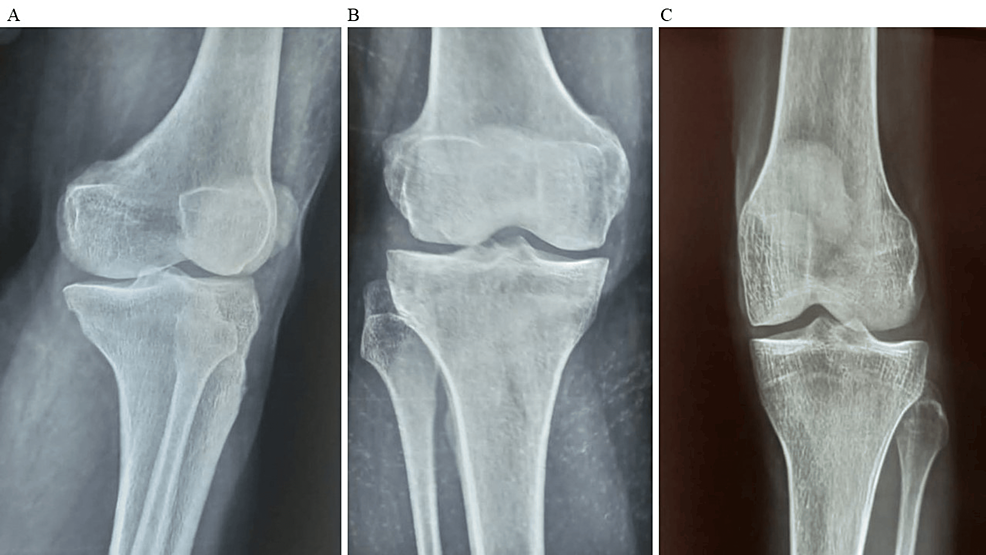

除了骨關節(jié)炎外,15名參與者還被發(fā)現(xiàn)患有骨缺損,占該隊列的30%。這些缺損包括各種情況,例如骨折、退行性骨病或先天性畸形,突顯了研究中涉及的骨科問題多種多樣。下圖1顯示了開始干細胞治療之前的骨骼側(cè)視圖和前后視圖。

圖1:顯示了開始干細胞治療之前的骨骼側(cè)視圖和前后視圖。

圖1:A:干細胞治療前(側(cè)視圖),B:干細胞治療前前后位(AP)視圖,C:干細胞治療前前后位(AP)視圖。